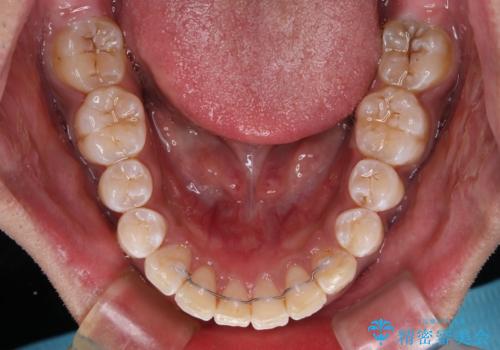

- 審美装置

- 2年2ヶ月

口元の突出感はあまりありませんでしたが、上顎歯列が全体的に前方にあり、更には下顎歯列が深く咬みこんでいるために、上顎前歯が前方に突出している状態でした。

抜歯は行わず、補助装置を用いて上顎歯列全体を後方移動させ、ワイヤー装置にて奥歯の咬み合わせを改善していくこととしました。

正面や横から見た印象が同じで用であっても、奥歯の咬み合わせが理想的であるかどうかによって、治療の難易度は大きく異なります。

こちらの方も難易度のやや高い状態で、2年以上の期間が予想されましたが、想定通りの2年強で治療を終えることができました。